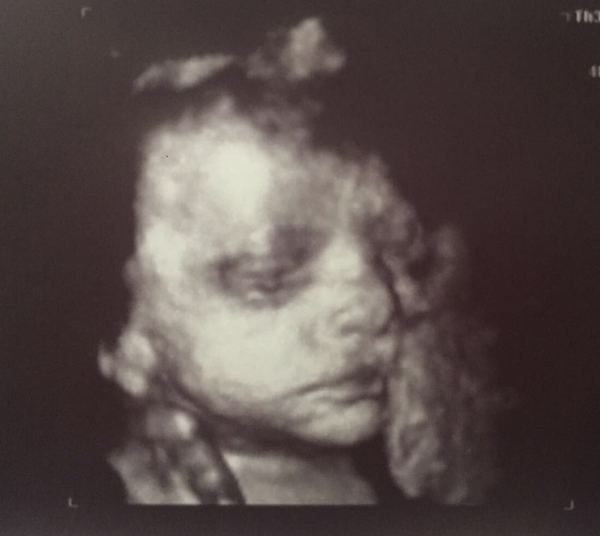

Had the scan today ladies, it was really good. Baby all on track and weighing in at 3 and a half pounds. Everything was average for 30+4. It had it face covered by my placenta the whole time so was tough to get good pics, but managed to get some. Was yawning and opening and closing its eyes, sucking its hand, really was amazing to watch.

Lovely pic @LuciBee231015 - must make it feel so real! I don't think I'll get a 4D scan as we still have 2 more growth scans and I nagged DH for so many early scans. I am tempted tho!

Luci that is a lovely image. Such detail! Glad all is progressing well. Now I want one but DH is very against it. Oh well.

That's a lovely scan pic luci x